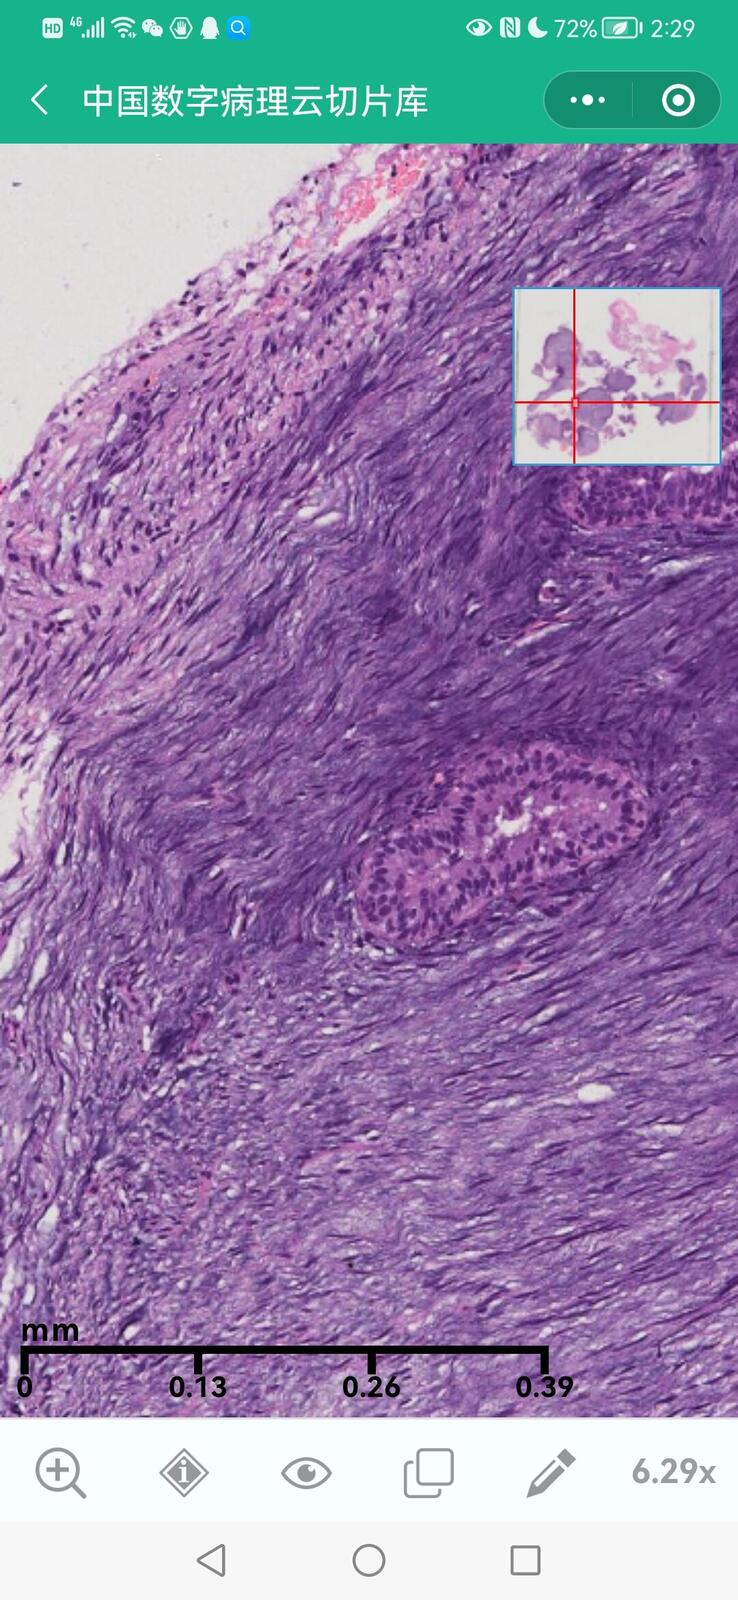

乳腺黏液性囊腺瘤伴导管内癌

乳腺多形性脂肪肉瘤

乳腺叶状囊肉瘤

乳腺分泌性癌(29岁)